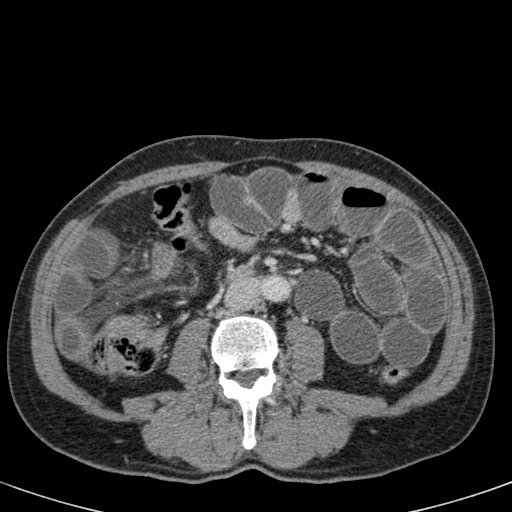

Nếu quai kín dài hơn và định hướng vuông góc với mặt phẳng cắt, chúng ta sẽ thấy một cụm quai ruột như trong ca lâm sàng bên trái.

Đôi khi điều này khó nhận biết chỉ trên các lát cắt ngang và các tái tạo mặt phẳng coronal hoặc sagittal có thể hữu ích.

Trong ca này, cũng có phù nề mạc treo và cổ

Bên trái là các hình ảnh CT bổ sung của cùng bệnh nhân nêu trên.

Hãy quan sát các hình ảnh này, tìm kiếm các dấu hiệu chính rồi tiếp tục.

Đầu tiên, chúng ta thấy đại tràng xuống xẹp và đại tràng lên không giãn, do đó đây không thể là xoắn đại tràng sigma.

Thứ hai, chúng ta thấy một cấu trúc hình mỏ chim ở góc phần tư dưới bên phải, đây là vị trí xoắn của ruột.

Ở góc phần tư dưới bên trái, chúng ta thấy manh tràng giãn.